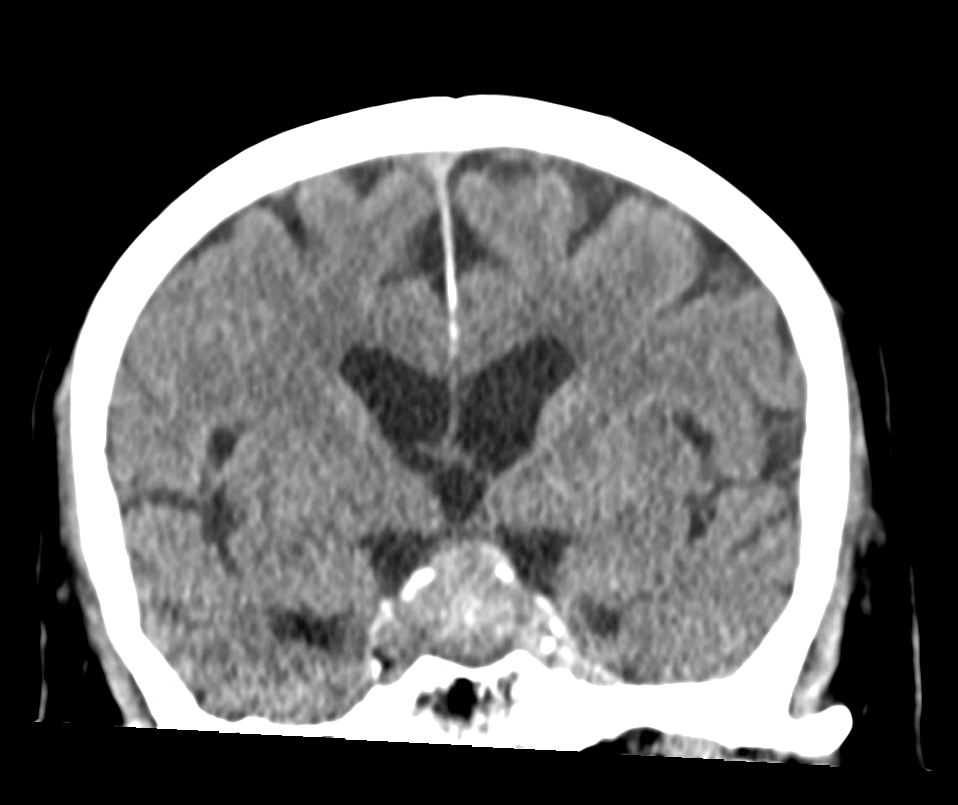

CT

Je nach Größe können Hypophysenadenome auch in einer CT Bildgebung dargestellt werden.